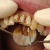

Nekrootilise hamba juureravi

... nekrootilist põletikukoldeta hammast ravida minimaalselt kahel visiidil Steriilne nekroos või apikaalne parodontiit Nekrootiline hammas on osutatud olevat steriilne kui röntgenpildil ei leidu periapikaalpiirkonna ...

Praktiline juureravi

... näidustused irreversiibel pulpiit akuutne krooniline pulbinekroos surnud infektsioonivaba pulp apikaalne parodontiit radikulaartsüst põletikuline resorptsioon sisene väline kirurgilised põhjused ...

parodontiit

Parodontiit varem parodontoos ehk hambapõletik on hammast ümbritsevate kudede haigestumine Enamasti on need koed põletikulised...

... välja. Parodontiidile eelneb alati gingiviit, kuid mitte igast gingiviidist ei pruugi areneda parodontiit. Parodontiit mõjutab kogu organismi! Parodontiidi korral on põletikust haaratud ja ...

Parodontiit on hamba kinnituskudede haigus. Haiguse algstaadiumis tekib hambakaelale hambakivi. Kivi tekib toidujääkide ja mikroobide (katu) mineraliseerumisel. Süljest liiguvad mineraalained kattu ja see muutub kivitaoliseks moodustiseks. Kivi on aga omakorda hea ja kare pinnas, kuhu pisikud hästi kinnituda saavad. Mikroorganismide...

Parodontiit on hambakatul ning ladestustel pesitsevate mikroobide poolt põhjustatud hambaid ümbritsevate kudede krooniline põletik, mille tagajärjel võib hävida hammaste kinnitusaparaat. Hambad hakkavad liikuma ning langevad lõpuks välja. Ravi on kompleksne ja pikaajaline ning seisneb eelkõige haiguse põhjuste väljaselgitamises ja kõrvaldamises....